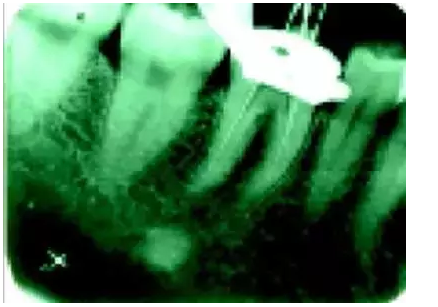

在傳統(tǒng)的根管治療中,開髓后往往只是依靠術(shù)者的視覺和經(jīng)驗(yàn)去尋找根管,所以常常存在遺漏根管的可能,從而導(dǎo)致根管治療的失敗。研究發(fā)現(xiàn),X線片上顯示根管充填滿意的患牙仍有癥狀的主要原因是有遺漏的根管未治療。

手術(shù)顯微鏡是用于尋找隱藏或遺漏的根管最重要的工具。因?yàn)槭中g(shù)顯微鏡能夠幫助醫(yī)生觀察到肉眼或普通放大鏡無法分辨的根管口和微小病損。在手術(shù)顯微鏡下,利用高倍數(shù)(16~24倍)的放大作用以及理想的照明條件,仔細(xì)檢查患牙的髓室底,許多細(xì)微的解剖結(jié)構(gòu)能容易被發(fā)現(xiàn)。

為了光線能充分進(jìn)入髓腔,髓室頂應(yīng)完全揭去,開髓口的形態(tài)應(yīng)根據(jù)具體牙位進(jìn)行適當(dāng)修改,使得所有根管口都能夠充分暴露。同時(shí),對髓底進(jìn)行美藍(lán)染色也有助于根管口和微小病損的識別。

術(shù)前應(yīng)首先根據(jù)X線片了解根管的鈣化程度、位置、根管的彎曲度、牙位等信息。開髓后,在顯鏡下仔細(xì)探察辨別鈣化根管和正常牙本質(zhì),避免破壞健康牙本質(zhì)結(jié)構(gòu),然后使用特殊的超聲工作尖(如ET40、ET20等)可以較容易地疏通鈣化根管。

有時(shí)超聲預(yù)備根管可能會深達(dá)距根尖幾個毫米。治療過程中需配合使用根管銼進(jìn)行探查并拍X線片檢查,防止器械偏離根管長軸,如此反復(fù)操作直到疏通根管并到達(dá)根尖。需要注意的是由于X線片僅能反映二維重疊影像,當(dāng)切削方向向頰側(cè)或舌側(cè)偏移時(shí),不易診斷。為了軟化鈣化組織,術(shù)中推薦使用17%EDTA進(jìn)行根管沖洗。